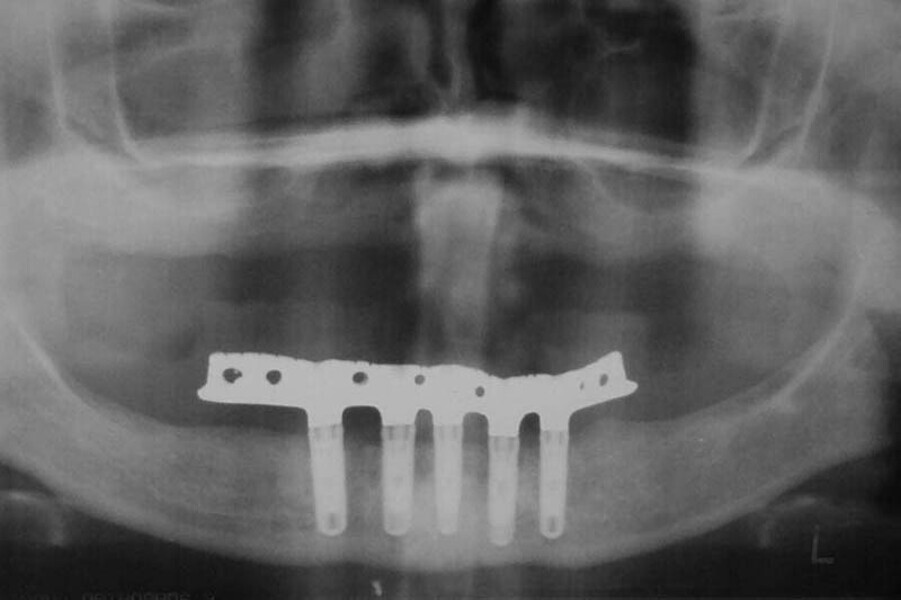

Fig. 8. Rx Pre-operatoria, Prótesis híbrida inmediata con 10 años de evolución y Rx Control a los 10 años.